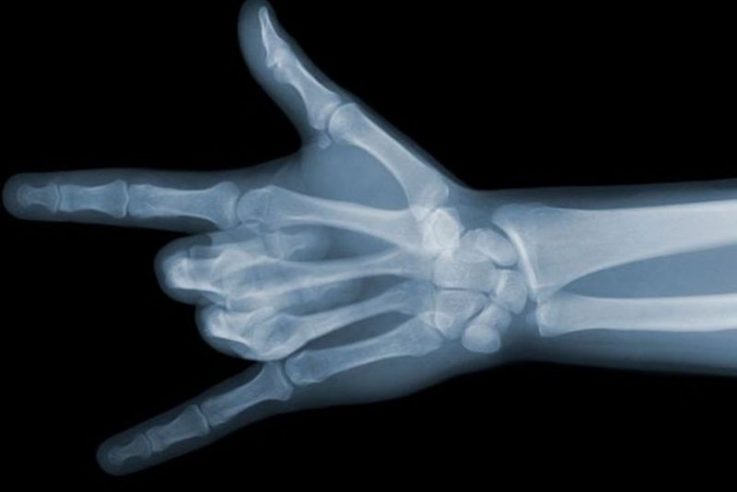

Лікарі розповіли, чи небезпечний для здоров’я рентген

Лікар-терапевт розповіла, чи небезпечний рентген та як часто його робити.

Сучасна діагностика дає можливість у найкоротші терміни виявити небезпечні хвороби. Найбільш поширений метод діагностики – рентген, який допомагає лікарю завадити хворобі ще на початковій стадії, пише aif.

Лікар-терапевт Наталія Носко, розповіла, які існують види променевої діагностики та як часто потрібно робити рентген. Фахівець запевняє, що рентген менш ефективний, ніж КТ та МРТ. Після рентгену отримуємо сумарний знімок (наприклад, від грудної клітки до лопаток).

Рентгенографія і КТ – рентгенівські методи дослідження. Під час їх проведення людина отримує певну кількість шкідливого випромінювання. Під час МРТ знімок отримуємо внаслідок магнітно-ядерного резонансу. Людина при цьому не отримує шкідливого променевого навантаження.

Діагностику потрібно робити за призначенням лікаря, оскільки кожен вид дослідження має свої показання та ризики. Однак пам’ятайте, що рентген легень для профілактики усім треба робити регулярно – 1 раз на рік.